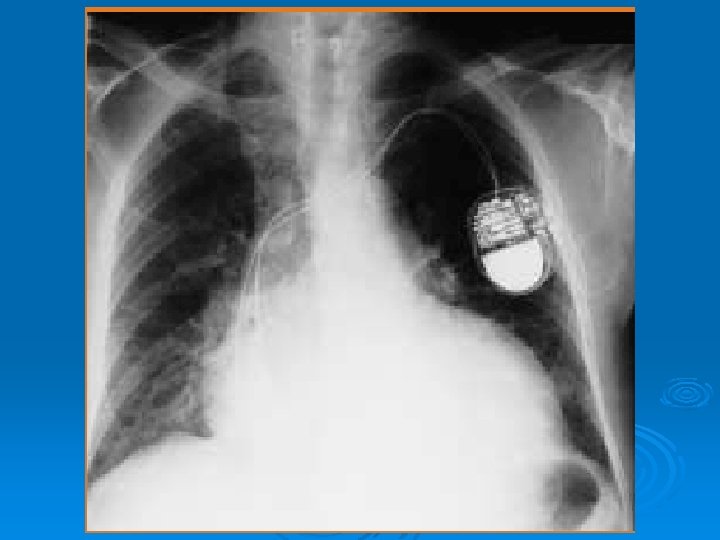

RECONOCIMIENTO DE CUERPOS EXTRAÑOS O IMPLANTES UTILIZADOS PARA TRATAMIENTO MEDICO